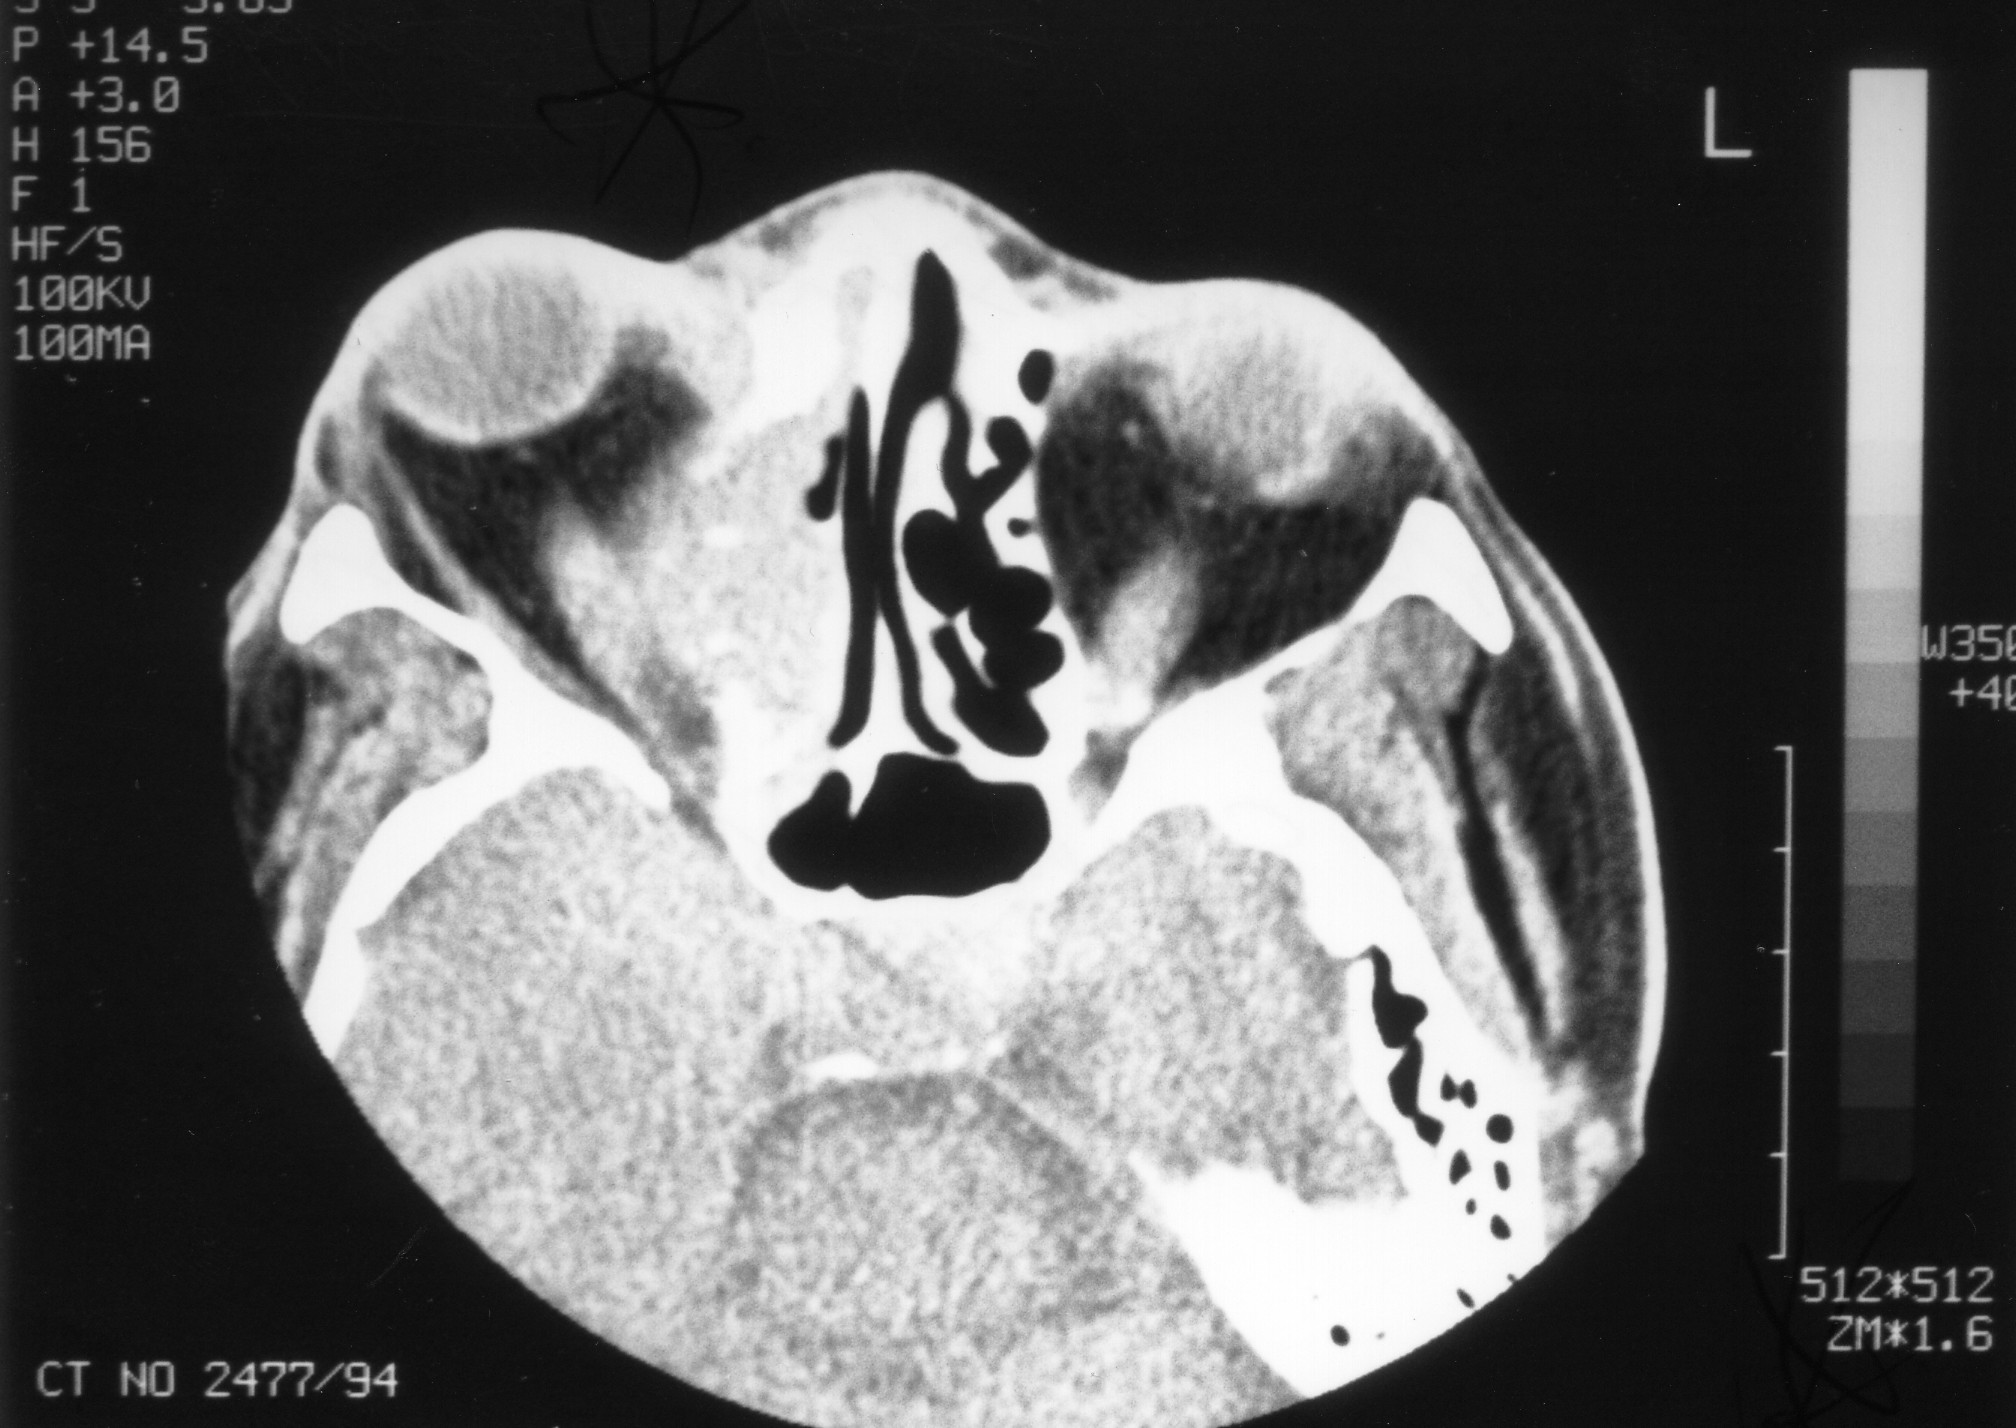

Background: Complications of acute inflammatory sinusitis into orbital and intracranial sepsis is a common problem in paediatrics.A delay in making a diagnosis and early appropriate treatment has a high morbidity and mortality rate.The commonest presenting symptoms are throbbing headache and facial or periorbital swelling usually fallowing a two week history of upper respiratory tract infection..A high resolution Computed Tomography(CT) scan is very helpful in making a proper and accurate diagnosis.Appropiate early medical and surgical treatment has a good outcome.We are reporting our epidemiological study of complicated sinusitis of 59 cases treated at Dr George Mukhari Hospital ,ENT Department a Tertiary referral centre, Medunsa Campus,University of Limpopo, RSA. Methods: A prospective case series of all patients admitted with complicate inflammatory confirmed on CT scan between April 2004 to August 2005(Winter months).An interview data collection sheet was used to collect all clinical information . . Results: Fifty-nine (59) inpatients (50 males and 9 females) admitted and treated at DGMH for complicated pan-sinusitis.The mean age of the patients was 13 years, with a male:female ratio of 7:1. All patients presented with a sporadic first episode of sinusitis, occurring within two weeks of upper airway infection. The affected age group was mainly paediatric of peripubertal age. In almost all the patients, headache and facial (peri-orbital) swelling were the main presenting symptoms. Most patients (85%) were initially referred to other departments 59.3% (35) to Ophthalmology, 18.6% (11) to Neurosurgery, 6.7 % (4) to Paediatrics and only 15.2 % (9) directly to ENT (Otorhinolaryngology). Of these patients, 36 (61%) had intracranial complications confirmed on CT scan and were managed in consultation with the neurosurgeons and ophthalmologists. No major surgical complications were reported. Staphylococcus species were the most common organisms isolated; however, 50% of the pus swabs had a negative culture. Medical treatment based on culture and sensitivity, together with surgical drainage, achieved good results. Three females with severe complications died during the period of the study, but there were no male deaths reported in this study, even though more males than females were affected. Conclusions: Complications of septic sinusitis are a common problem in the paediatrics, with males more commonly affected than females. Females, however, had a poorer prognosis than males in this study. Complicated sinusitis should be suspected in any adolescent with orbital, facial or frontal swelling associated with headache always during the winter (cold) months. To prevent morbidity and mortality, a high resolution contrasted CT scan is mandatory for the exclusion of complicated sinusitis,medical and surgical treatments are effective management of complicated sinusitis